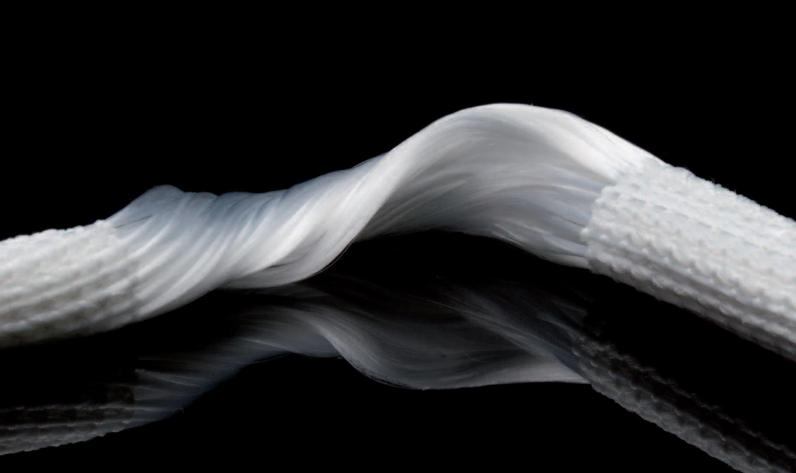

经与患者及家属沟通后,建议手术治疗,骨二科专家团队告知患者三种移植物的优劣势后,患者及家属坚定地说:“还是用人工韧带吧,不想取自体肌腱,有点拆东墙补西墙的意思,也怕取肌腱部位疼痛;更不想别人的肌腱放在自己身体里,可能排异,也容易再断裂。”

图3 LARS韧带 图4 术中LARS韧带重建

LARS人工韧带为一种新型生物材料,具有优异的生物相容性和力学性能,能够模拟人体自身韧带的生理功能。与传统自体或异体肌腱移植相比,由于人工韧带不需要从自身部位取材,从而减少手术创伤,避免供区疼痛、肌肉力量下降及其它并发症,人工韧带的强度更是人体肌腱的3-4倍,术后便可承受较大的物理负荷,许多患者更早开始康复训练,加快术后恢复过程。